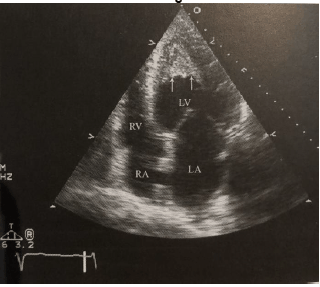

No acometimento das câmaras direitas, pode haver ascite volumosa, hepatomegalia e elevadas pressões de enchimento. E, apresenta um achado característico ao ecocardiograma transtorácico visto na imagem abaixo.

Sobre ele, assinale a alternativa correta.

Paciente do sexo masculino de 75 anos, iniciou há cinco anos quadro de episódios recorrentes de dispneia aos esforços e edema de membros inferiores necessitando frequentemente buscar atendimento médico de urgência, não é portador de doença hipertensiva nem de outras comorbidades. Na última visita ao setor de urgência, apresentou-se com quadro clínico de insuficiência cardíaca biventricular e edema de extremidades. À investigação com exames complementares foi realizado ECG que evidenciou complexos QRS de baixa voltagem.

Assinale a alternativa correta que contém o provável diagnóstico, de acordo com os dados acima e a imagem ecocardiográfica abaixo.